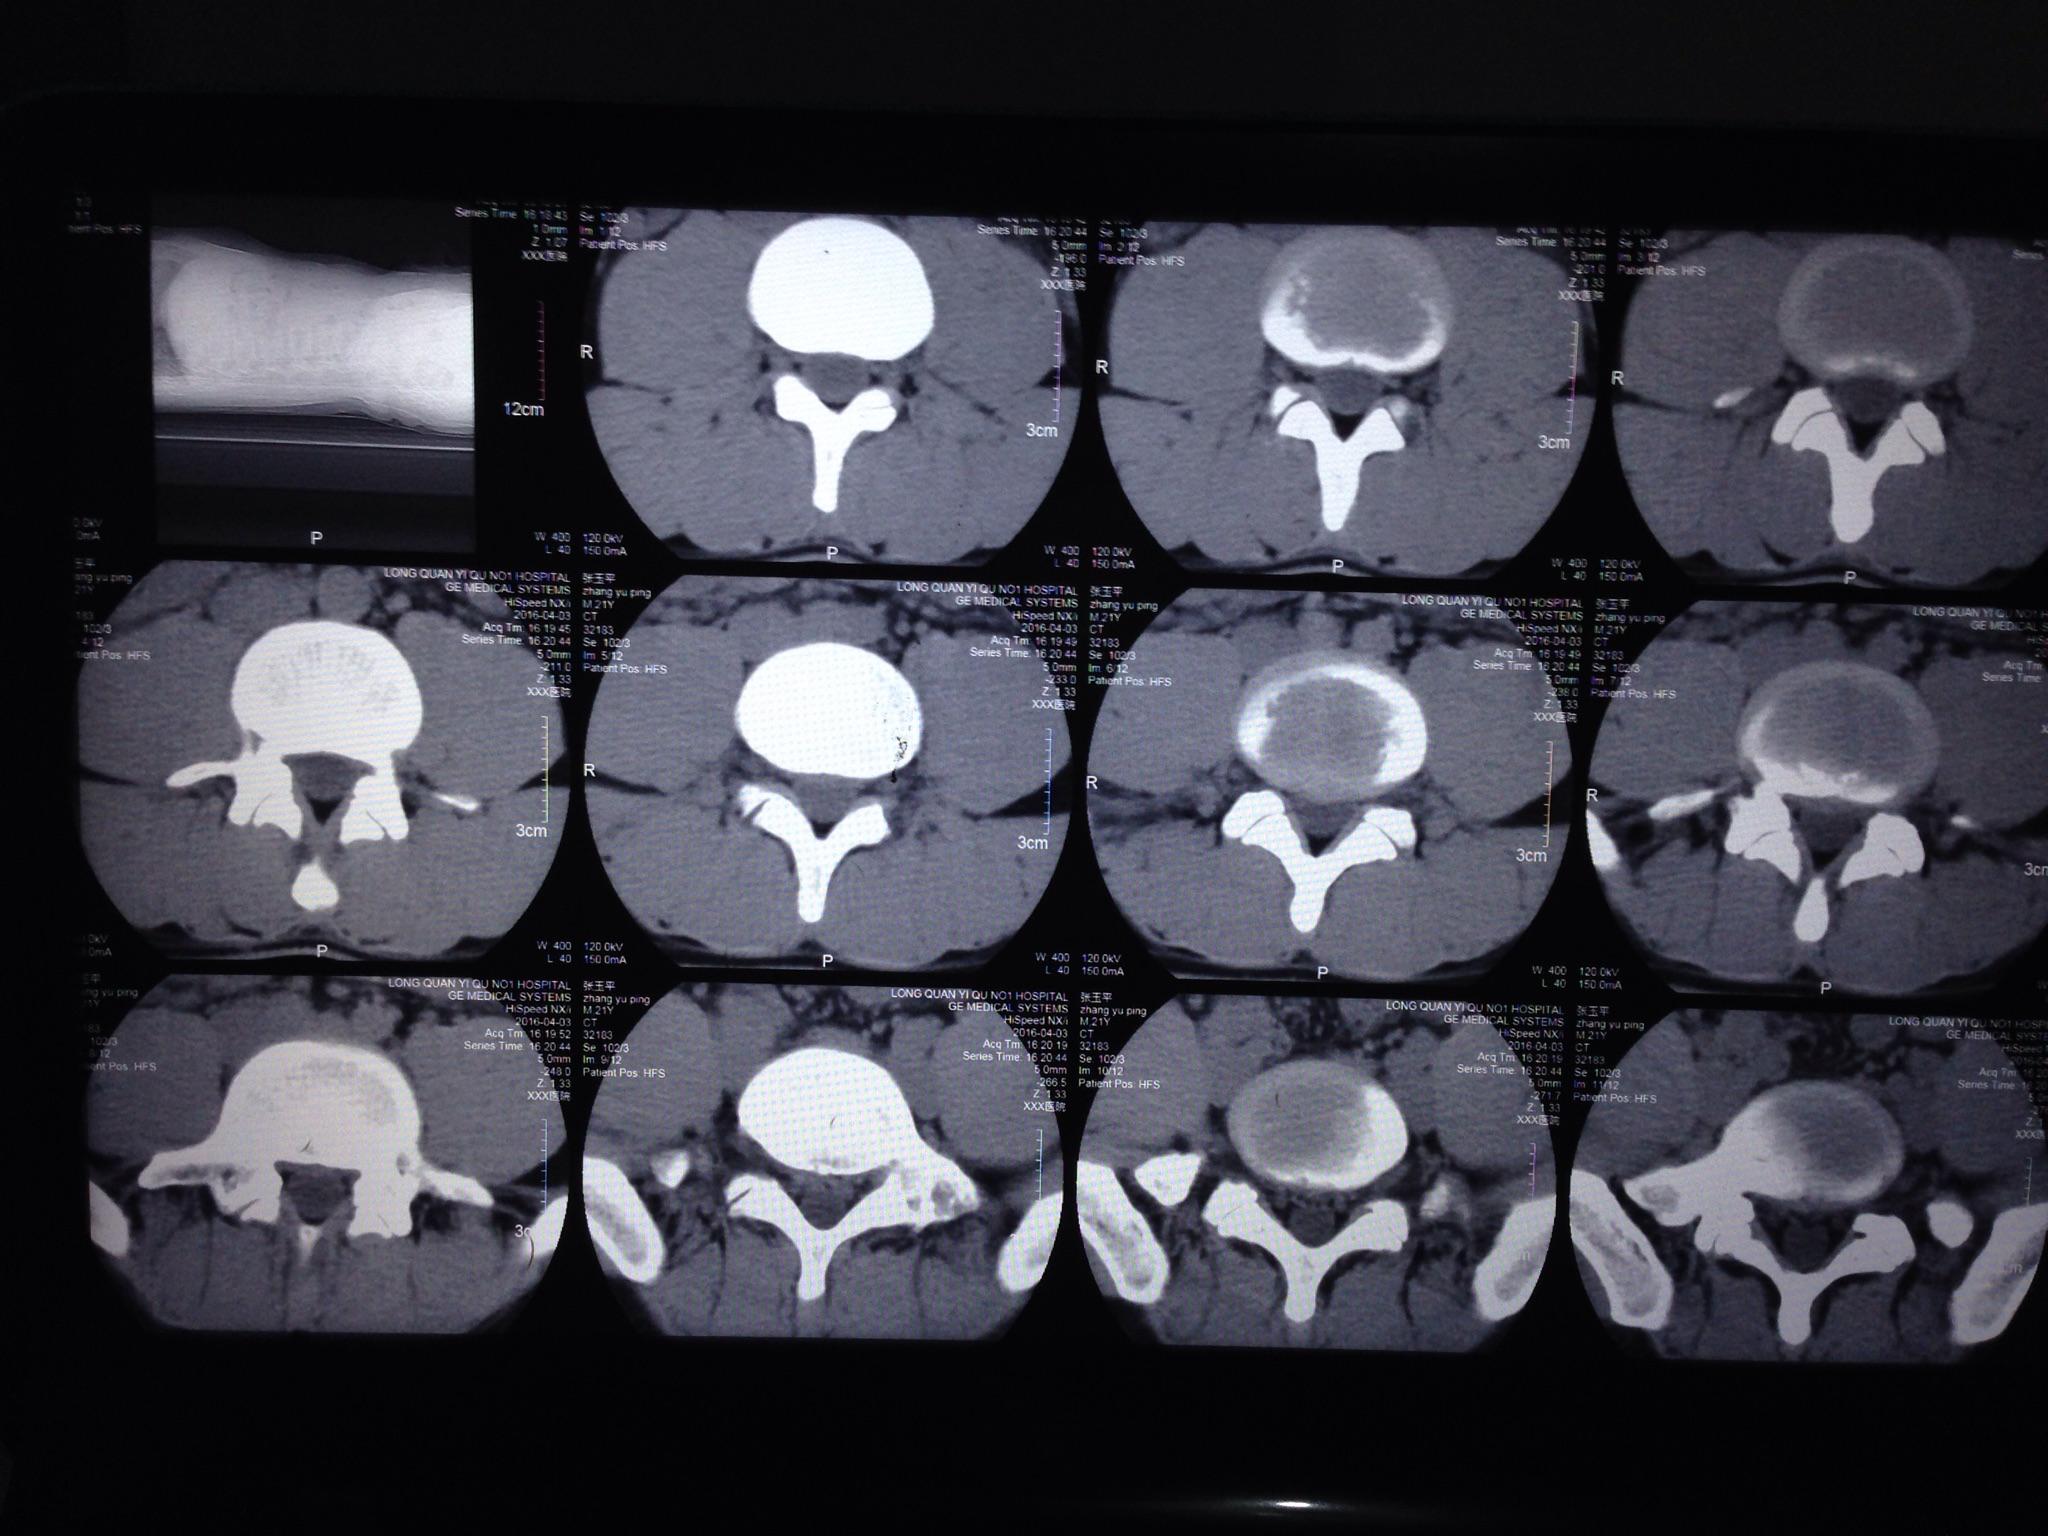

ct片显示腰椎l3/4椎间盘向左侧脱出,硬膜囊和神经根严重受压 .

图片尺寸1080x1440

c t l3/4向左侧突出,硬膜囊受压,l5/s1中央型突出偏右硬膜囊受压.

图片尺寸1200x1600